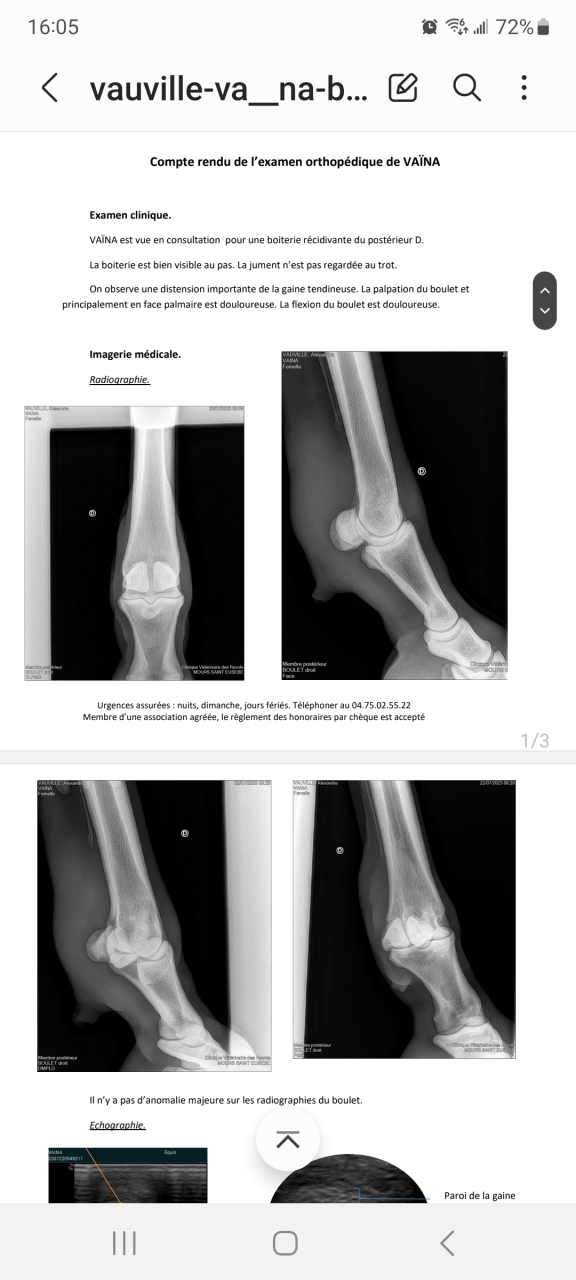

| Dire merci | Lésion du tendon superficiel, grosse inflammation de la gaine et gros épanchement. Donc on attend l'avis du chirurgien si il faut opérer. Inflammation de la parois de l'os mais légère là où elle s'est mise coup. La premier veto à pas fait les radios et l'écho au bon endroit. Donc on a pas pu comparer l'évolution. Voilà voilà on est parti pour quelques mois de soin. |

| Dire merci | Je vous met le compte rendu de l'echo ![]() |

Par kagnotte : le 23/07/23 à 16:06:33

| Dire merci | Et les radios![]() |

| Dire merci | Donc voilà je pense qu'on est parti sur quelques mois de galère. Et si certain ont des expériences sur ce type d'intervention je prends. Je ne sais pas encore quelle décision prendre. |